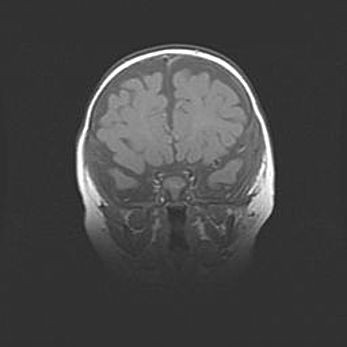

Церебральная ишемия II.

Возраст: 5 дней

Вес: 3400 г

Пол: женский

Окружность головы: 35 см

Срок гестации: 39 недель

Церебральная ишемия – это заболевание, характеризующееся недостаточностью (гипоксией) либо полным прекращением (аноксией) снабжения мозга кислородом по причине закупорки одного или нескольких сосудов. Это приводит к  что метаболическим расстройствам различной степени тяжести в тканях головного мозга, развитию коагуляционных некрозов и гибели нейронов.